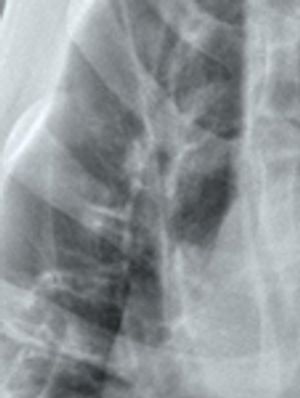

Megaesophagus is a condition in which the esophagus has reduced peristalsis, and has poor tone at rest. The esophagus can have a mild, focal motility problem, or the entire organ may be dilated and functioning poorly.